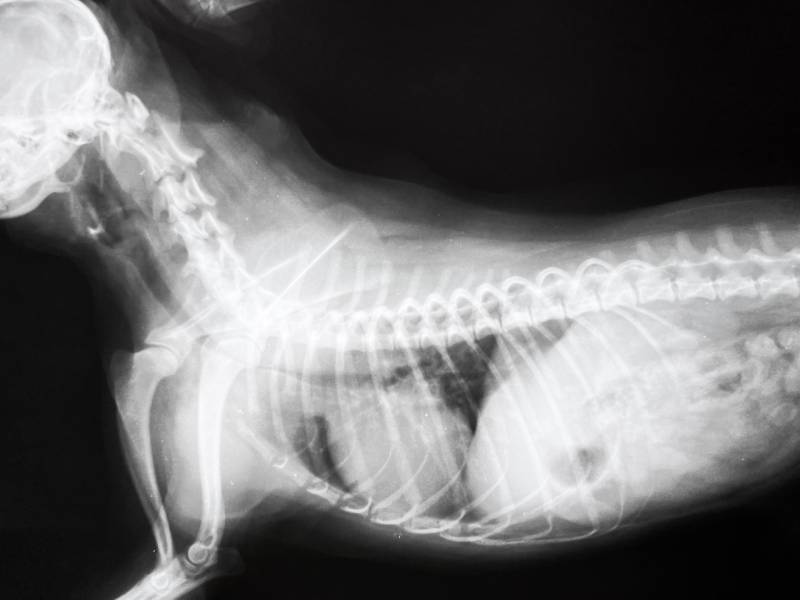

Can A Dog Die From A Collapsed Trachea . Here's how to best support your dog with this condition. The disease is caused by a defect in the cartilage rings that support the windpipe. Can dogs die from a collapsed trachea? A collapsed trachea in your dog is a serious condition, but it something that they can live with. Tracheal collapse (also known as collapsed trachea or collapsing trachea) is the narrowing of the windpipe that prevents the dog from getting enough oxygen and from getting rid of heat effectively. Dogs experiencing tracheal collapse will have: Tracheal collapse is a progressive respiratory condition that occurs when these tracheal rings of cartilage collapse. Read about how you can help your dog with this condition. In a dog with a collapsing trachea, the rings have lost some of their rigidity due to deterioration, so they squish down and enable that membrane of tissue to dip into the airway when a dog. A dry, chronic cough that makes them sounds like a honking goose; Symptoms of collapsed trachea in dogs. A dog with a collapsed trachea coughs like a honking goose.